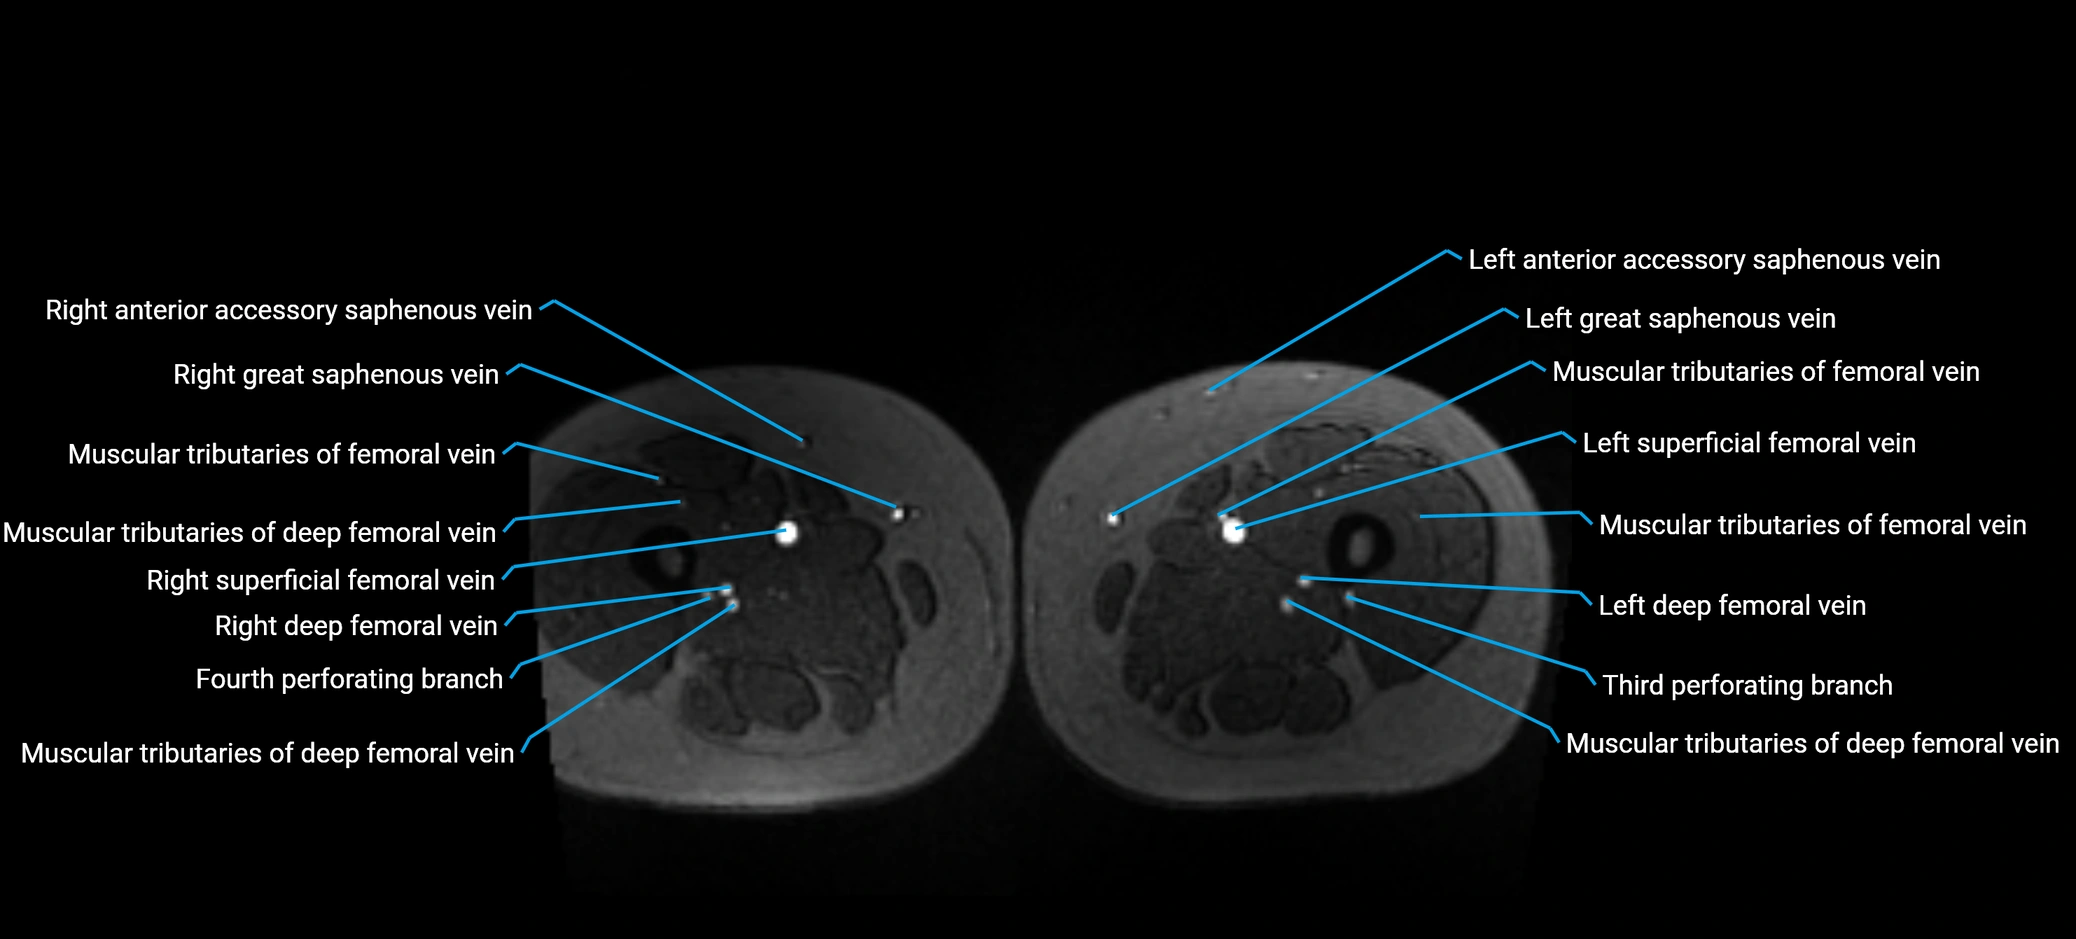

MRI image

image